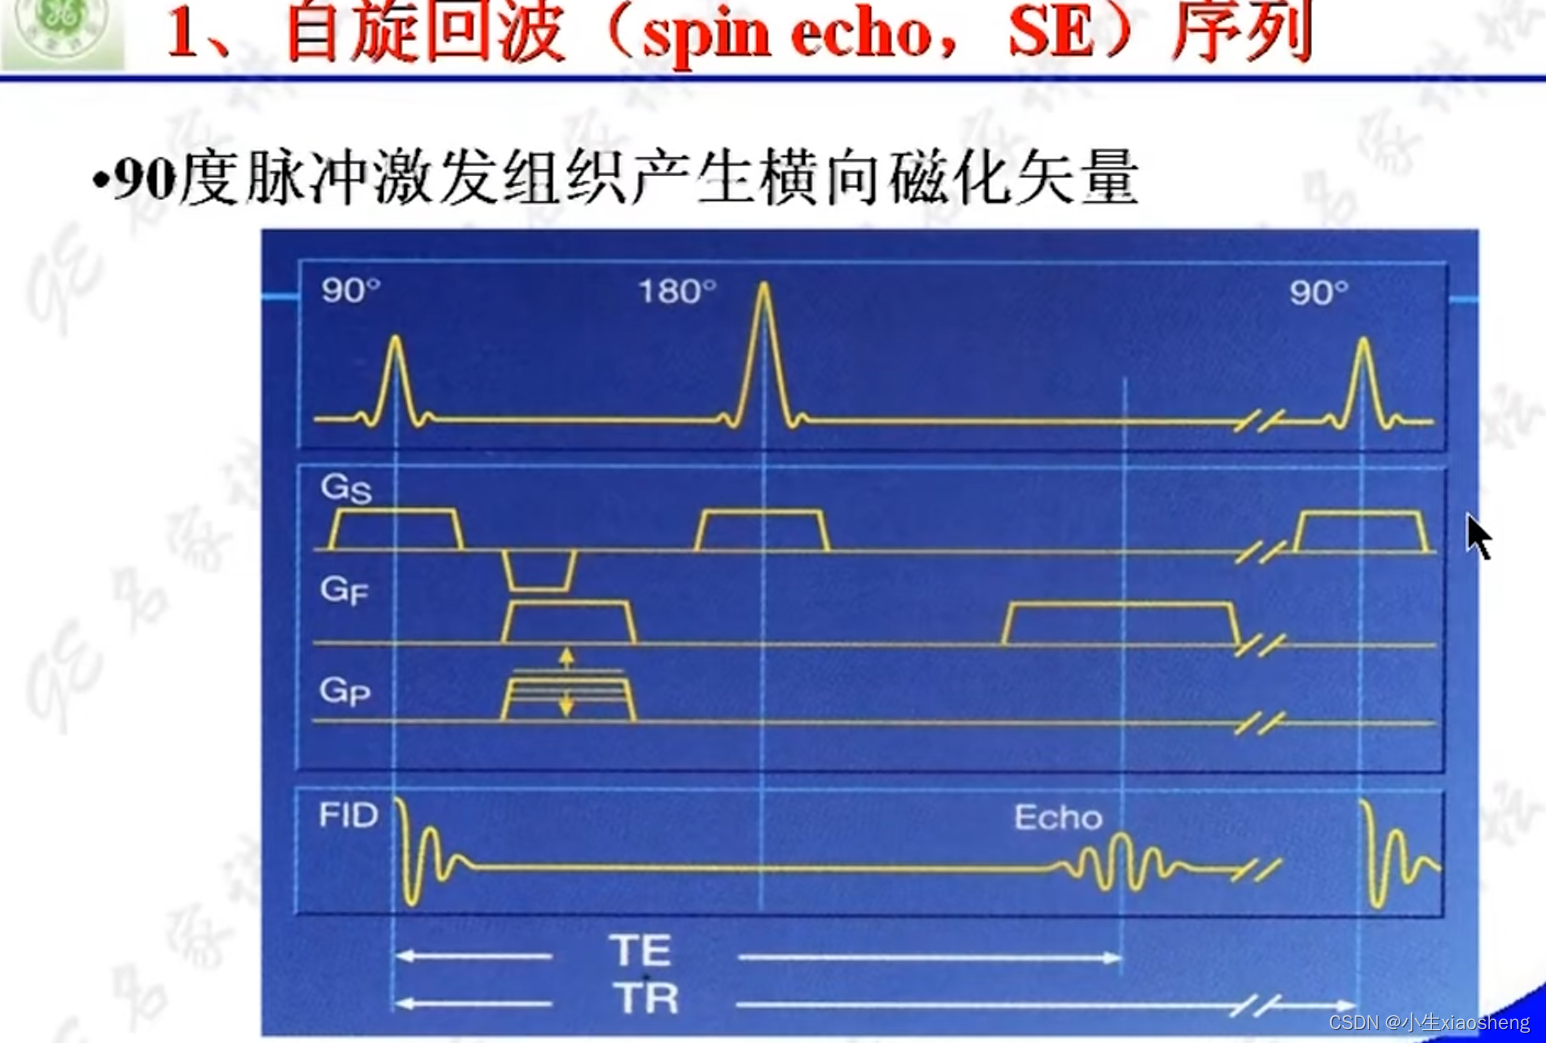

1.自旋回波序列SE

90度和180度共同来组成一条K空间线。

180度的意思就是改变终点的方向,恢复慢的离终点近,恢复快的离终点远,到时候一起到。这样就比原来的弛豫下降的时间要长了。